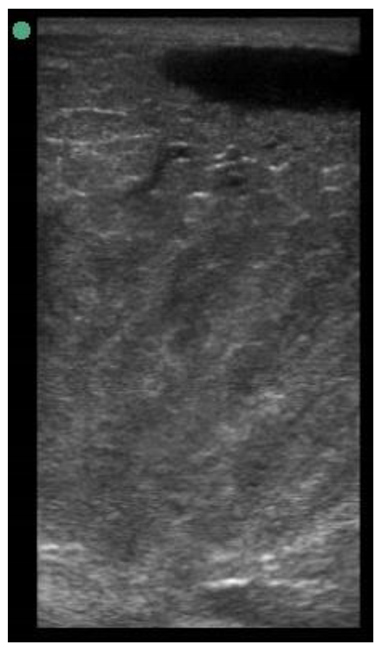

Appendix A. Drawing Templates of Mammary Ultrasound Images in Late Pregnancy, Early Lactation and Weaning in Yearling Ewes

Drawing template of mammary ultrasound images in late pregnancy (107 days of pregnancy; P107) in four different yearling ewes.

Drawing template of mammary ultrasound images in early lactation (29 days of lactation; L29) in four different yearling ewes.

Drawing template of mammary ultrasound images at weaning (100 days of lactation; L100) in four different yearling ewes.